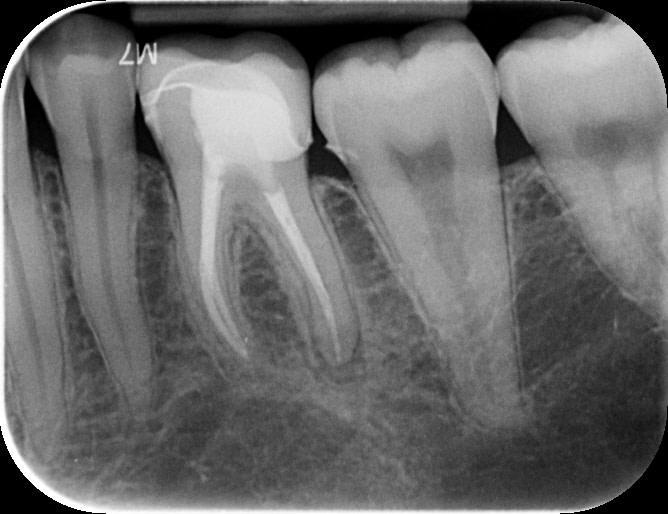

Pre op PA showing periapical radiolucency around 36D root apex.